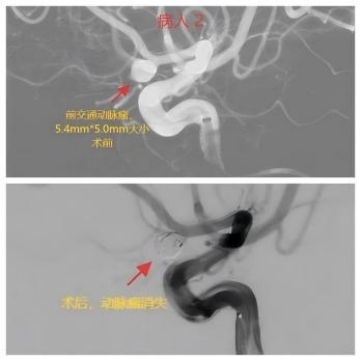

“急診來了一位78歲蛛網(wǎng)膜下腔出血的女病人,CT考慮動脈瘤破裂,病情危重!”神經(jīng)外科主任王磊的手機響起,傳來值班醫(yī)生的聲音,“好,立即啟動卒中綠色通道,通知介入導(dǎo)管室、麻醉醫(yī)生迅速到位,準(zhǔn)備急診手術(shù)!”。當(dāng)手術(shù)快結(jié)束時,急診又入院一位72歲的同樣的蛛網(wǎng)膜下腔出血的女病人,本該休息的醫(yī)生們再次穿上沉重的鉛衣與死神搏斗。經(jīng)過一夜的戰(zhàn)斗,兩個病人手術(shù)均取得成功。

我院目前已建立了完善的腦卒中綠色通道,能夠迅速、有效地完成從檢查、診斷、急診手術(shù)等流程。自今年1月份以來,我院神經(jīng)外科已接診了40多例動脈瘤破裂出血的患者。